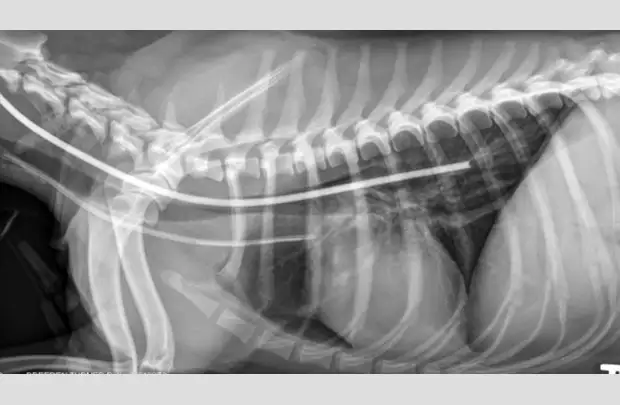

Ensure the tube is properly positioned via lateral radiography (A).

If placement is uncertain, infuse a small amount of nonionic contrast material to differentiate the esophagostomy tube from the endotracheal tube or jugular catheter (B).

If the tube is in the trachea, the portion running in the proximal cervical region will be visibly ventral to the esophagus on radiography (C).

Replacement of a blocked esophagostomy tube attempted with an awake patient resulted in collapse of the stoma, inadvertent placement of the tube (arrow) into the mediastinum, and subsequent mild pneumothorax.